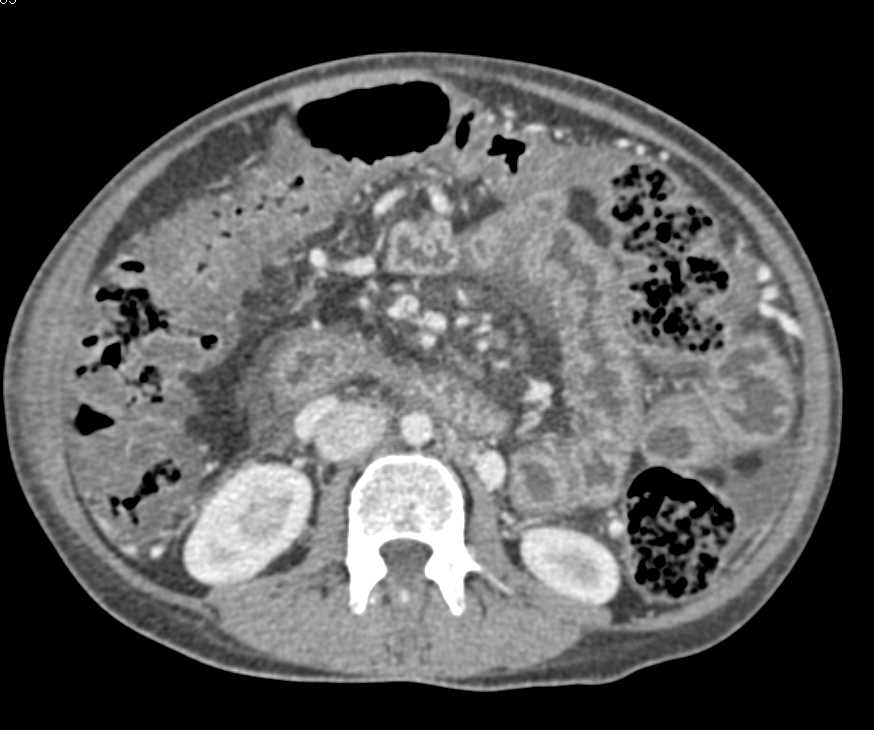

Active Bleed Near Splenic Flexure